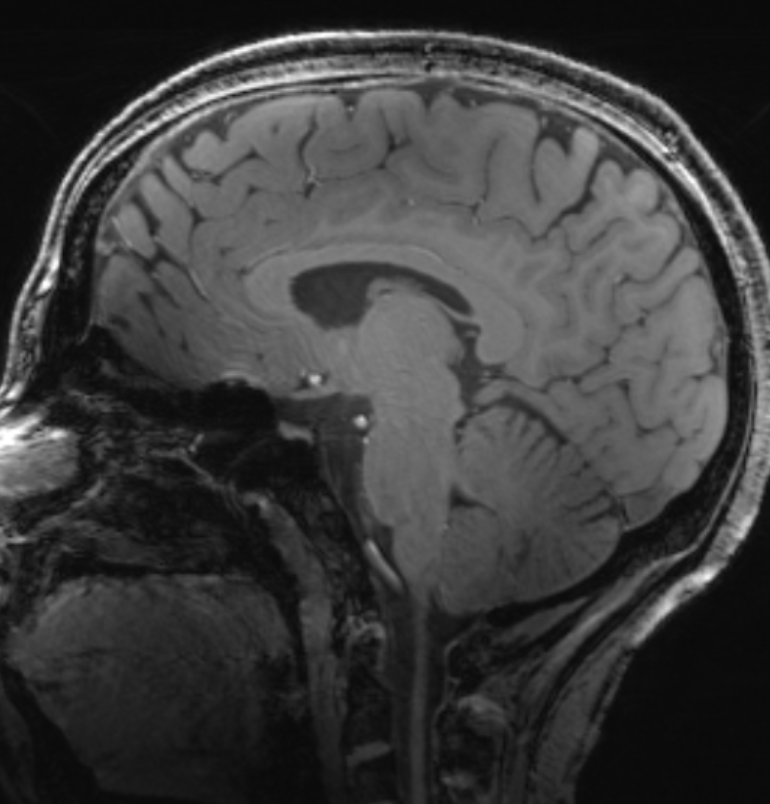

This project began with an assessment of the HSP community’s needs. All of the available published scholarly articles available on HSPs with a mention of white matter abnormalities were reviewed. The MRIs available in these articles were reviewed by 3 independent raters blind to the diagnosis of each MRI, and inter-rater consensus was reached.

The MRI findings were compiled into a database, along with additional information, and sorted by each gene. This database was then used to train an algorithm to detect and best-match white matter abnormalities that are seen on MRI. This algorithm was used to develop the tool found here.